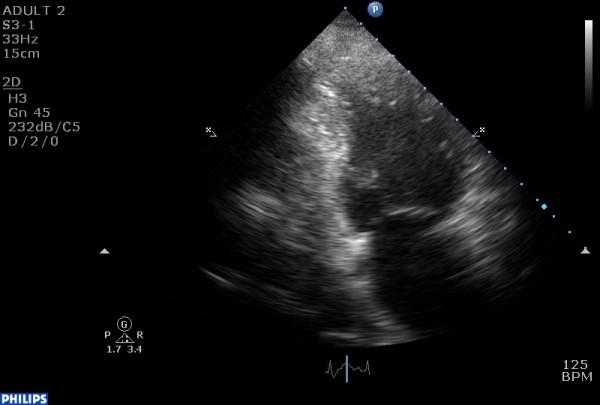

We report a case of a woman with transient myocardial injury after a stressful event, presenting with a variation of the affected segments. In this case, only the basal and mid portions of the left ventricle were affected, while the apex was completely spared. Coronary angiography revealed no significant occlusion and left ventricular function had recovered completely by the third day of hospitalization.

我们报告一例女性在应激事件后发生短暂性心肌损伤的病例,其受累节段有所不同。在该病例中,仅左心室的基底段和中段受累,而心尖完全未受累。冠状动脉造影显示无明显阻塞,住院第三天左心室功能已完全恢复。